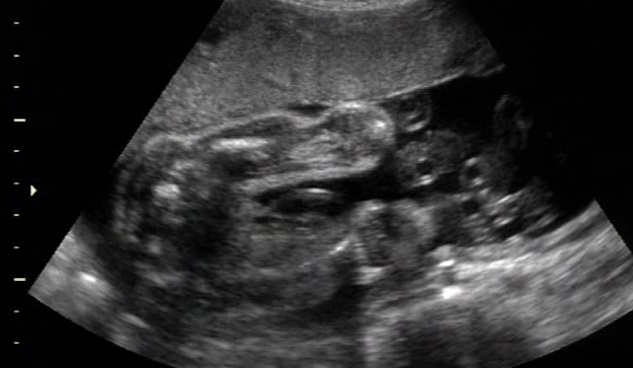

Baby Girl Ultrasound 20 Weeks 3 Days - YouTube

Baby Girl Ultrasound 20 weeks 3 days klhall494. Subscribe Subscribed Unsubscribe 2 2. 21W2D- 1st Ultrasound- Finding out the gender of our baby! - Duration: 7:16. ourlittlemushroom 157,014 views. 7:16 20 Week Ultrasound & Baby Bump Pics - Duration: 4:06. Montara Van Fleet 1,119 ... View Video